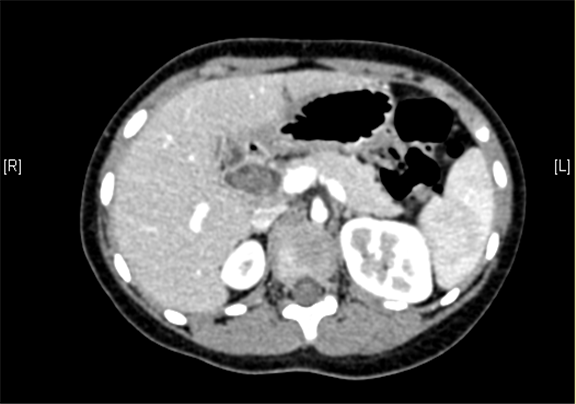

术前CT检查:

动脉期

静脉期

上腹部增强CT:1. 肝内部分胆管-肝门部胆管-胆总管扩张,符合先天性胆管扩张症2. 胆总管下段腔内结节状略高密度影,伪影?结石?3. 胆囊壁略厚,提示胆囊炎可能。